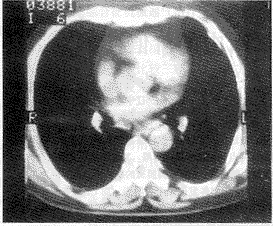

1.2.1 胸膜改变:X线片可观察到胸膜改变5例,其中1例疑为胸膜斑。CT检查发现胸膜改变高达16例,其中6例为胸膜斑,并可观察到胸膜斑钙化、小块的胸膜斑、表面不平及结节状表现(图1、2、3),还有3例脊椎旁胸膜斑(图3、4)。CT检查所见的改变在X线片上是难以发现的。

患者接触石棉15年(1949~1964年)

图1 CT检出左前侧非钙化型胸膜斑